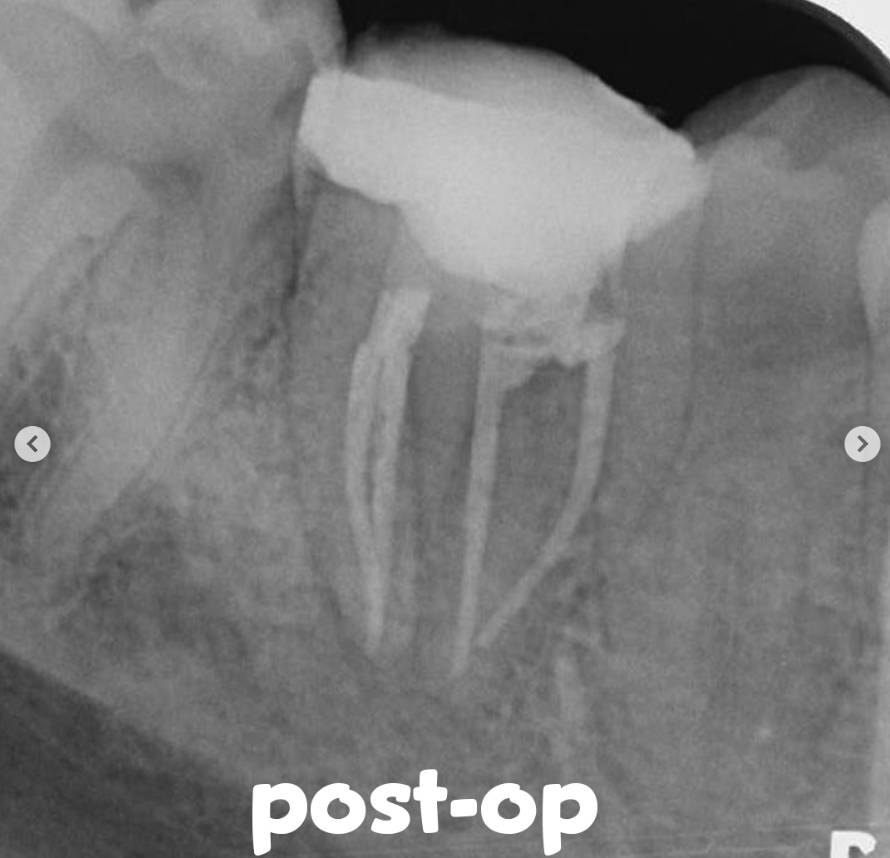

• Under rubber dam isolation, the coronal restoration was removed, revealing the furcation perforation area.• The separated file fragment was removed using ultrasonic activation.

• The perforation site was temporarily sealed with sterile teflon, and the previous root canal fillings were removed using retreatment rotary files.

• After achieving adequate preparation and irrigation, the root canal system was confirmed to be completely dry, and the canals were obturated with gutta-percha and a resin-based sealer.